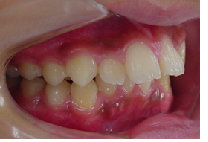

当矯正歯科医院ではMEAW法(マルチループ)で治療する事で非抜歯で治療しています。

MEAW法(マルチループ)を利用することで以下の様に上顎前突が改善されていきます。

終了時